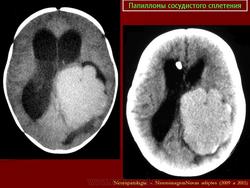

Папилломы сосудистых сплетений.

Хориоид папиллома макроскопически имеет вид «цветной капусты», т. е. узла с мелкогранулярной дольчатой поверхностью, темно-красного цвета, плотной консистенции с преимущественной локализацией в просвете желудочков. Опухоль хорошо отграничена от стенок желудочка и имеет тесную связь с сосудистым сплетением. Исключение составляет хориоидкарцинома, которая прорастает мозговое вещество на большом протяжении. Значительная часть этих новообразований локализуется пара- и перивентрикулярно. Под микроскопом типичная хориоидпапиллома имеет строение, аналогичное структуре ворсин сосудистого сплетения. Она представлена скоплениями сосочков различного размера и формы. Сосочки обладают стромой в виде сосудистого стержня и выстланы слоем многорядного хориоидного эпителия.